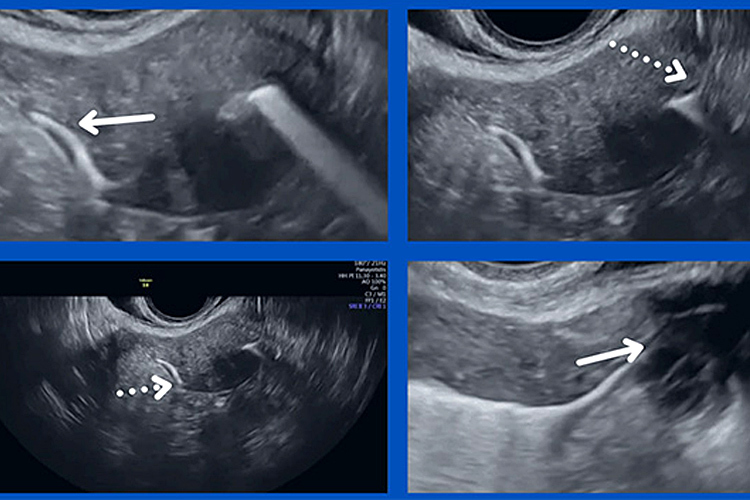

Σε αυτό το σημείο ο γιατρός θα κοιτάξει για να δει εάν το υγρό περνά από την κοιλότητα της μήτρας στις σάλπιγγες. Εάν το υγρό φαίνεται να εκχύνεται από το άκρο κάθε σάλπιγγας, αυτό θα επιβεβαιώσει τη διαβατότητα των σαλπίγγων. Εάν το υγρό δεν φαίνεται να περνά από τη μία ή και τις δύο σάλπιγγες μπορεί αυτό να υποδηλώνει ότι υπάρχει στένωση ή φραγμός της σάλπιγγας ή των σαλπίγγων. Σε αυτήν την περίπτωση θα πρέπει να προβούμε στη διαγνωστική μέθοδο σε ό,τι αφορά τη διαπερατότητά των σαλπίγγων, η οποία είναι η διαγνωστική λαπαροσκόπησή (ώστε να επιβεβαιωθεί ή όχι η γνωμάτευση του υπερήχου). Αυτό θα συζητηθεί με λεπτομέρεια και θα κανονιστεί εάν χρειάζεται αργότερα και όχι κατά τη διάρκεια του τεστ HYFOSY.

Εικόνες παραδείγματα: τα βέλη δείχνουν τα σημεία όπου το σκιαγραφικό περνά και δείχνει διαπερατή την σάλπιγγα.